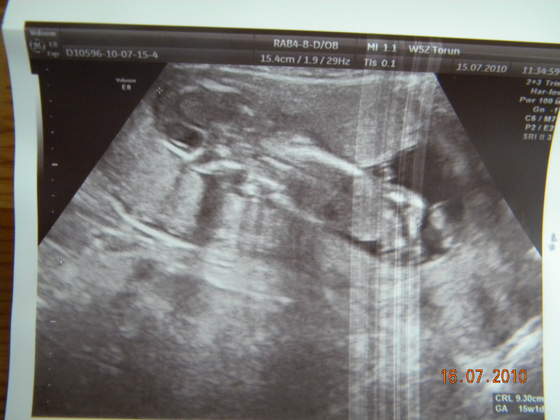

byliśmy z brzuszkiem wczoraj na wizycie kontrolnej i udało nam się namówić ginka na usg ;-)nawet nie specjalnie dał się prosić

ginek mówił że tylko takie szybkie usg zrobimy, a wyszło dłużej niż usg przezierności karkowej

Kajetanek (?) rośnie jak na drożdżach i ma już 9,30 cm, ginek chciał zajżeć pomiędzy nóżki ale wstydzioszek je podkurczyłi na koniec odwrócił się do nas dupką

Zobacz załącznik 265045Zobacz załącznik 265046